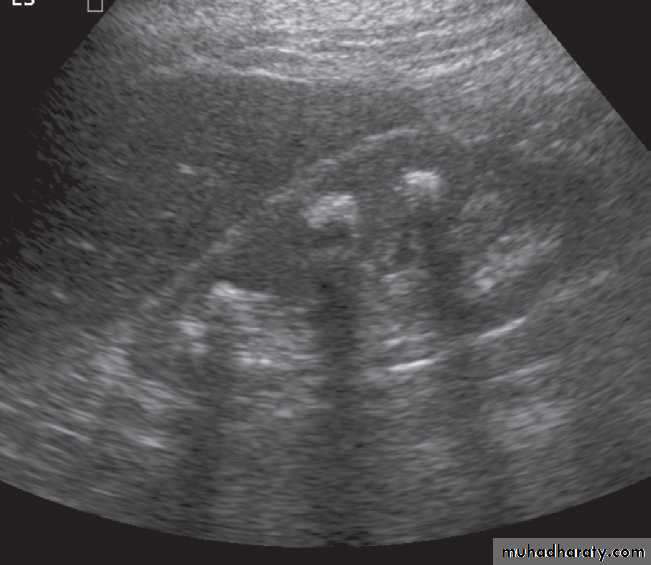

U/S :Most renal calculi of more than 5 mm in size are readily seen at ultrasound, produce intense echoes and cast acoustic shadows.

Stones in the ureters cannot be excluded on ultrasound, although stones lodged at the vesicouteric junction may be demonstrated .